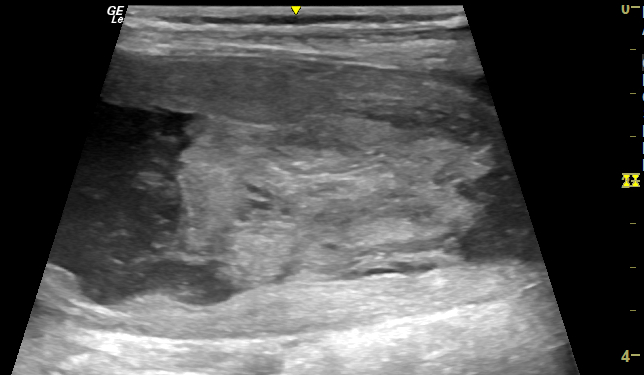

Urethral obstruction is another of those scenarios where ultrasound is under-used. Like azotaemic cats, I feel that they pretty much all benefit from being scanned. This is a recent patient, a male cat obviously, 24 hours after a difficult unblocking and who still has an indwelling urethral catheter. Several things to take from this: … Continue reading